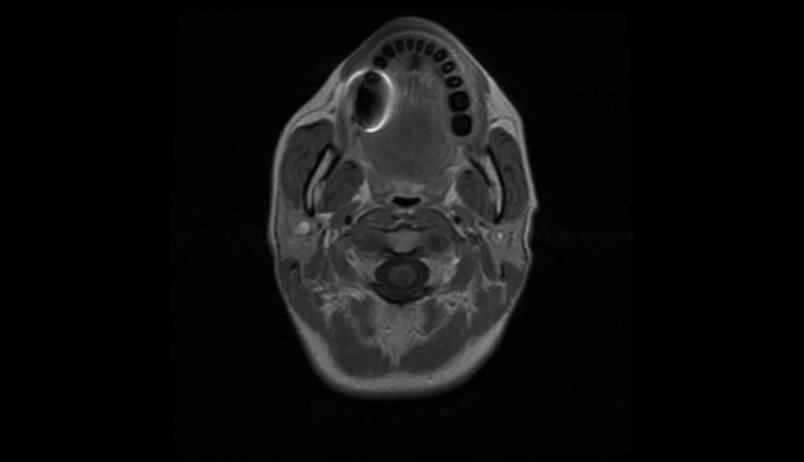

MRI of the cervical and thoracic spine showed a diffuse, intramedullary abnormal signal extending from the medulla down to approximately the mid-thoracic level. There was swelling in portions of the spinal cord, particularly in the lower cervical cord where there was contrast enhancement (Figure 1 [Fig. 1], Figure 2 [Fig. 2], Attachment 1 [Att. 1]). The MRI of the brain was normal.

Figure 2: MRI of the cervical spine, coronal view: contrast enhancement in the lower cervical cord

The impression was of subacute transverse myelitis. Multiple sclerosis and tumor were less likely. IV methylprednisolone was given. She had lumbar puncture and CSF studies done. CSF was clear. There were lymphocytes and monocytes with no malignant cells. Borrelia Burgdorferi IgG and IgM in the CSF were <0.80 index. No oligoclonal bands were detected. Herpes Simplex virus 1 and 2 DNA were <80 copies/mL. Mycoplasma, coxiella, anaplasma, cryptococcus and hepatitis B were all negative. Acyclovir ordered by the emergency doctor was discontinued the next day. She had a peripherally inserted central catheter (PICC) placed and was given IV ceftriaxone for 7 days and subsequently maintained on doxycycline for a 21-day course. No other processes were identified. Symptoms did seem to improve clinically. The patient stayed in hospital for 8 nights and was discharged in stable condition.